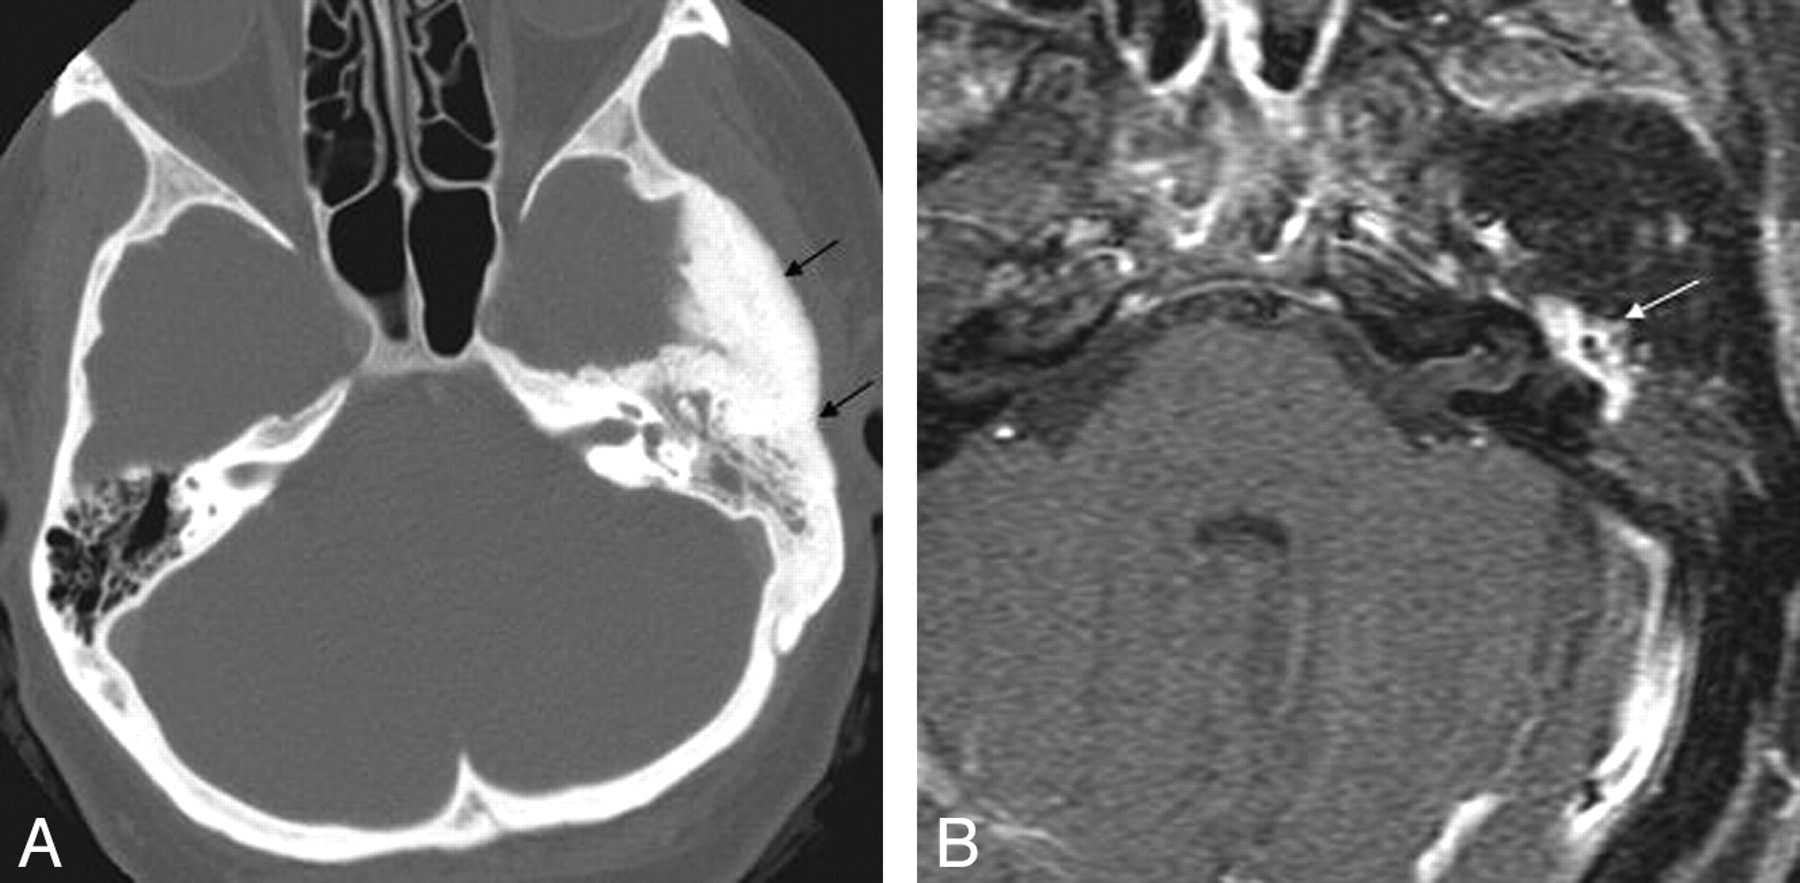

Intraosseous meningiomas of the temporal bone or skull base can occasionally present with tinnitus28 and mimic sclerotic fibrous dysplasia on imaging. CT characteristically demonstrates thickening of the tegmen tympani, but the internal trabecular architecture of the involved bone is preserved (Fig 6A). This feature has been termed “trabecular” hyperostosis to distinguish it from the bone thickening observed in cortical hyperostosis or fibro-osseous lesions. Characteristic MR imaging findings include en plaque linear dural enhancement along the floor of the middle cranial fossa and homogeneous soft-tissue enhancement (Fig 6B).29

Intraosseous temporal bone meningioma in a 45-year-old woman who presented with left-sided hearing loss and tinnitus. A, Axial CT image demonstrates diffuse sclerosis of the temporal bone and soft-tissue attenuation (black arrows) in the left mastoid and middle ear cavity. B, Axial enhanced MR image in the same patient demonstrates enhancement within the left middle ear (white arrow).